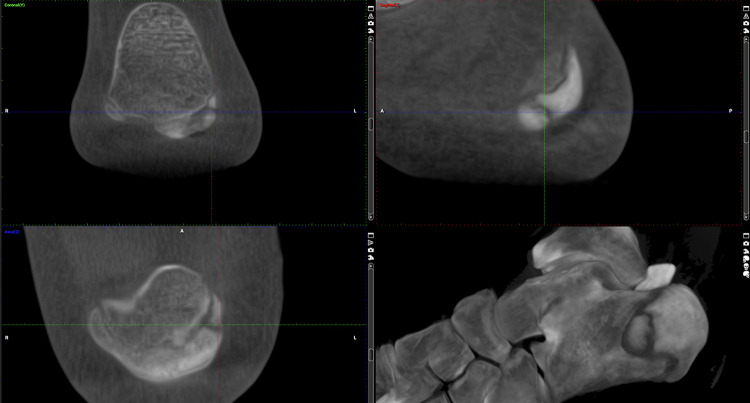

本病例报告描述了一种新颖独特的电磁和电液聚焦体外冲击波疗法(ESWT)与体外磁传导疗法(EMTT)相结合的治疗方法,用于加速一名青少年跑酷运动员胫骨骨骺骨折的愈合。在一次 2.5 米的跳跃后,这名 14 岁的少年出现了明显的足跟疼痛,但他没有告诉父母。八周后,使用超低剂量负重锥形束 CT(WBCT)进行的初步成像显示,在开放的小方骨骨骺附近存在小方骨骨骺不愈合的情况。为了显著改善并加快骨愈合,我们选择了联合使用聚焦电磁(Storz Ultra,Storz Medical AG,瑞士泰格威伦)和聚焦电液(MTS,德国康斯坦茨)ESWT,每周连续五次,同时让患者完全负重。六周后进行的 WBCT 随访显示,延迟结合部接近完全愈合,且无疼痛。值得注意的是,聚焦 ESWT 和 EMTT 联合疗法并没有导致小骨骨骺提前闭合。我们的结论是,聚焦电磁和电液 ESWT 与 EMTT 联合疗法可促进青少年小头骨骺骨折的骨性愈合,而不会对开放的骨骺产生任何不良影响。证据等级 IV(病例报告)。

This case report describes a novel and unique combination of both electromagnetic and electrohydraulic focused extracorporeal shockwave therapy (ESWT) and extracorporeal magnetotransduction therapy (EMTT) for accelerated healing in a calcaneus epiphyseal fracture with delayed healing in an adolescent Parkour athlete. After a 2.5m jump, the 14-year-old experienced significant heel pain, however avoided telling his parents. After eight weeks, the initial imaging using ultra low dose weight-bearing cone beam CT (WBCT) revealed a calcaneus non-union situation adjacent to the open calcaneal physis. To improve and accelerate bony healing substantially, we chose to apply both combined focused electromagnetic (Storz Ultra, Storz Medical AG, Tägerwillen, CH) and focused electrohydraulic (MTS, Konstanz, Germany) ESWT in a fractioned fashion plus EMTT (Storz Magnetolith, Tägerwillen, CH) in five consecutive weekly sessions while allowing the patient to fully weight bear. The follow-up WBCT after six weeks revealed a near to total healing of the delayed union and being pain-free. Notably, combination therapy with focused ESWT and EMTT did not result in early closure of the calcaneal epiphysis. We conclude that combined focused electromagnetic and electrohydraulic ESWT and EMTT facilitate bony healing in adolescent calcaneal apophyseal fractures without any adverse effects on the open physis. Evidence level IV (case report).